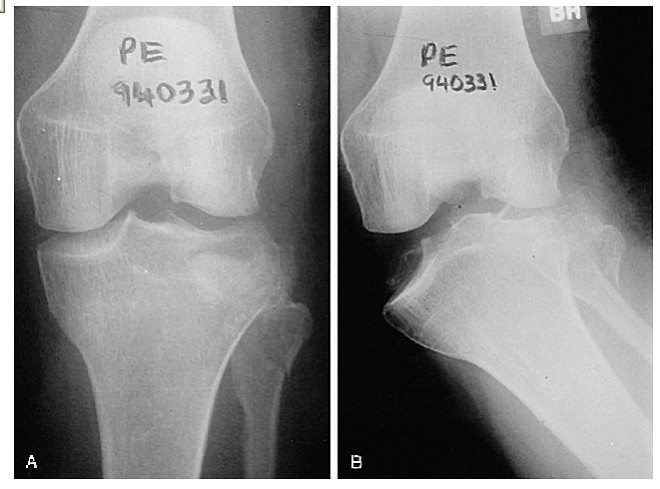

These fractures can be quite subtle and should always be considered when assessing acute knee injuries. Usually the common patterns of tibial plateau fractures are identified on plain films (AP, LAT, OBLIQUES).

Significantly displaced tibial plateau fractures are usually treated by internal fixation.